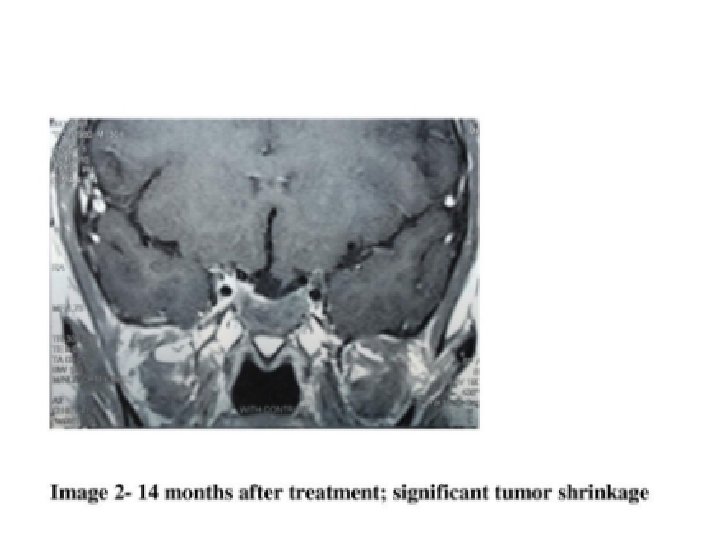

Macroadenoma management • Medical therapy regardless of size • Reassess vision within one month if initially abnormal (improvement may be observed within a few days) • Adenoma size decrease within weeks or months and can continue for years

Treatment • Medical: Dopamine agonists • Bromocriptine: initial dose, 1. 25 mg nightly, increased to 2. 5 mg bid in 1 -2 weeks, Doses larger than 7. 5 mg/d are seldom needed but in macroprolactinoma Microprolactinoma: 85%-90%: Nl. PRL in within days to a few weeks, Regular menses: a few months Macroprolactinoma: visual field improvement within 1 -3 days and reduction in tumor size as soon as 2 weeks • Cabergolin: more effective than bromocriptine Surgical: trans-sphenoidal

Monitoring of macroadenoma therapy • Normal PRL > 1 years and markedly decreased size: decrease the dose gradually to keep PRL normal • Discontinue if initial size was 1 -1. 5 cm and PRL normal >2 yrs and no mass lesion by MRI • Monitor PRL and Size indefinitely • Macroadenoma not met above criteria should be treated even after menopause